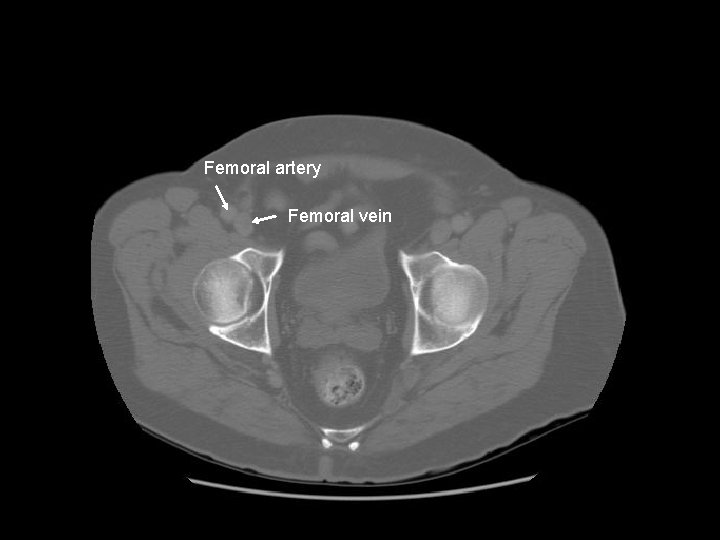

Femoral artery Femoral vein

Femoral head Acetabulum